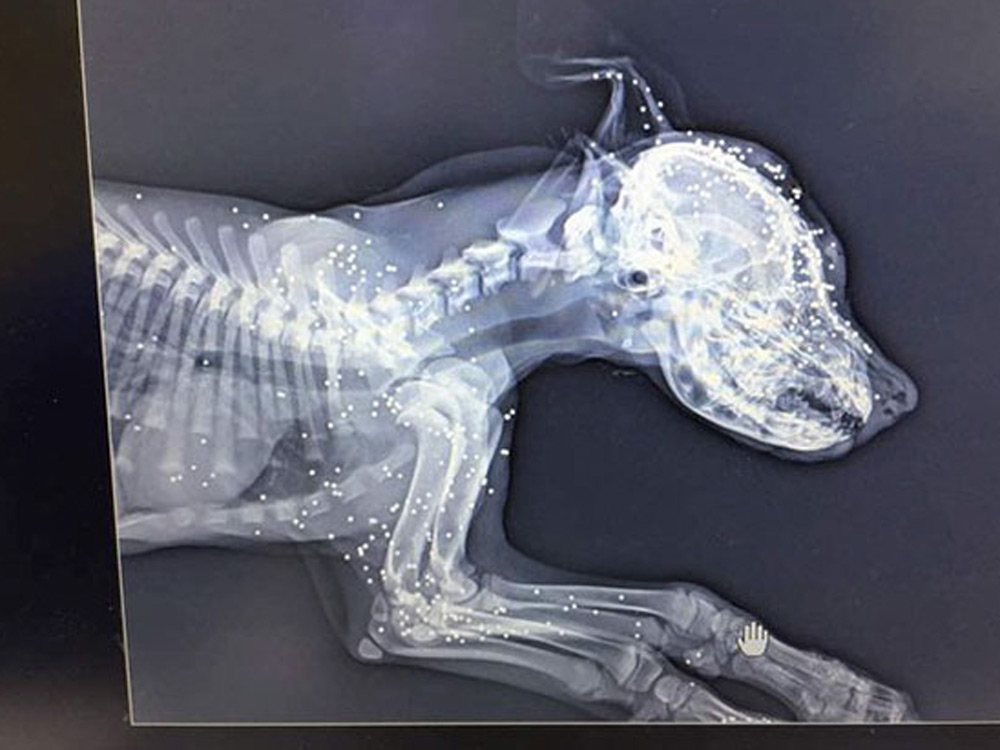

Los escáneres de rayos X mostraron que la perra tenía el cuerpo lleno de perdigones y que había sido disparada decenas y decenas de veces. Andari sugirió que probablemente había sido algún grupo de adolescentes buscando diversión ya que en su país eso, junto a los envenenamientos a animales, es muy frecuente. Algo que su organización “Animals Lebanon” busca cambiar.

Las radiografías mostraron algo horrible

El veterinario decidió hacerle unas radiografías para ver el estado de sus huesos y lo que descubrió fue horrible...

Había sido disparada decenas y decenas de veces

Las radiografías mostraron que tenía el cuerpo lleno de disparos. Pero no había sido una o dos veces sino que tenía decenas y decenas de perdigones incrustados en su cuerpo.